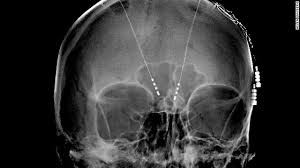

I wouldn't advise going to bed while wearing so much make up.

1. Your comment about sleeping with so much makeup is hilarious. I was thinking: "Wow, her eyebrows are perfect". Then, your comment - marvellous. Thanks for the interesting blog.